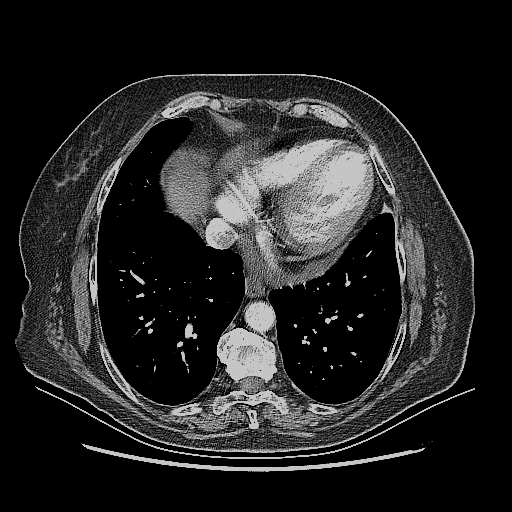

Original NATIVE CT scan (input)

Mediastinum window (WL 40, WW 400 β†’ Low βˆ’160, High +240)

Reconstructed NATIVE CT scan (cycle consistency)

Original VENOUS CT scan

Generated VENOUS CT scan (A→B translation)